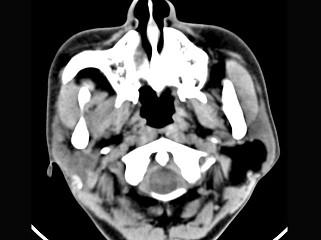

问题 男性38岁,左侧腮腺渐进性肿大一年,无压痛,CT扫描如图所示,请选择正确的描述和结论 ( )

选项 A、考虑为脂肪瘤 B、考虑为血管瘤 C、肿块边缘清楚,未见邻近结构受侵 D、考虑为囊肿 E、左侧腮腺区见低密度肿块,CT值约为-200Hu

答案 ACE